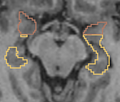

• Segmentation of the hippocampus using a multi-scale shape based method.

We represent and learn the shape in a multi-scale method and then perform the segmentation of the hippocampus.